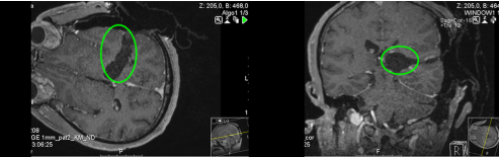

术前:术前MRI显示较大丘脑占位,肿瘤压迫导致明显体征。

术后:术中磁共振检查,显示肿瘤准确全切。手术顺利,无手术并发症。术后组织病理学检查弥漫性中线神经胶质瘤,WHO 4级。患者术后当天即拔出气管插管,无任何问题。术后3天即在物理治疗下增加康复锻炼,下地锻炼,术后5天即可自行站立行走。术后半年复查,肿瘤没有复发,患者症状好转。